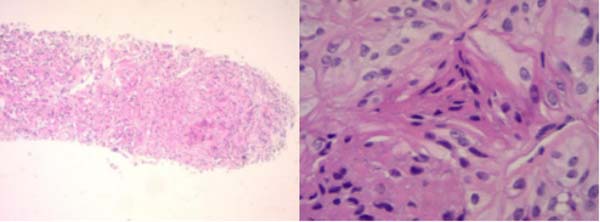

甲状腺-粗针活检:瘤细胞排列呈小梁状、器官样结构,细胞梭形或呈多角形,长轴垂直于基底膜,胞质丰富,嗜酸或透明,核沟及核内假包涵体易见,未见核分裂象,细胞巢间可见透明变的基底膜样物质沉积。

HTT通常表现为单侧单发有包膜的结节,界限清楚,切面实性、分叶状,灰白至淡黄色。镜下肿瘤以形成小梁状优势结构为特征,或呈实性巢状、腺泡状结构,间质富于窦状毛细血管;肿瘤细胞梭形或呈多角形,胞质丰富,嗜酸或透明,长轴垂直于基底膜,核的特征类似于PTC,核沟及核内假包涵体易见,核周可见特异性黄色小体,核分裂象罕见。瘤细胞巢间可见大量透明变的基底膜样物质沉积,PAS染色及胶原Ⅳ免疫组化染色阳性。HTT细胞核的特征与PTC有重叠,针吸细胞学易误诊为PTC,HTT细胞学示甲状腺滤泡上皮细胞丰富,围绕淀粉样透明变基质呈放射状排列,无乳头及滤泡结构,无平铺细胞片,细胞核拉长呈梭形,核膜不规则,核沟及核内假包涵体易见,胞界不清。Marina N. Nikiforova等研究表明,与PTC不同,GLIS重排在HTT中较普遍,特别是PAX8–GLIS3重排,这种融合基因导致GLIS过表达,进一步上调细胞外基质基因引起胶原沉积,从而产生镜下肿瘤组织中胶原丰富的现象。